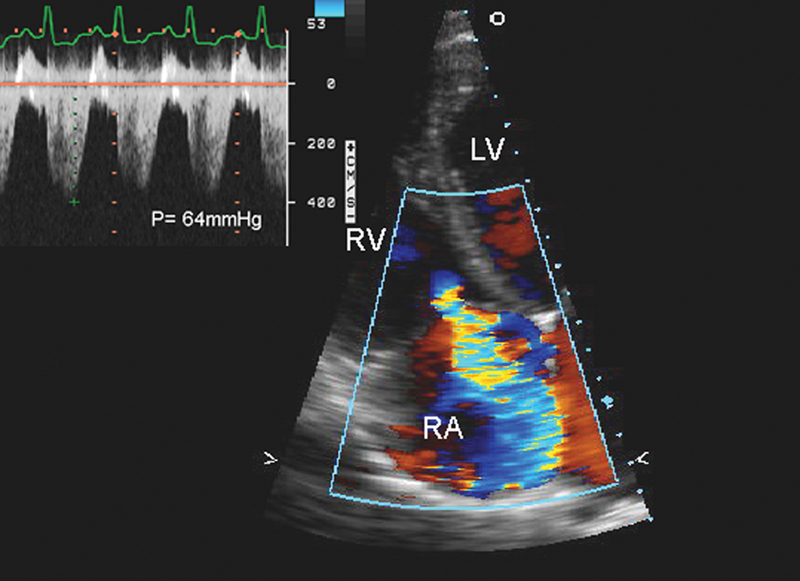

فحوصات تشخيصية لبعض امراض القلب والشرايين التاجية